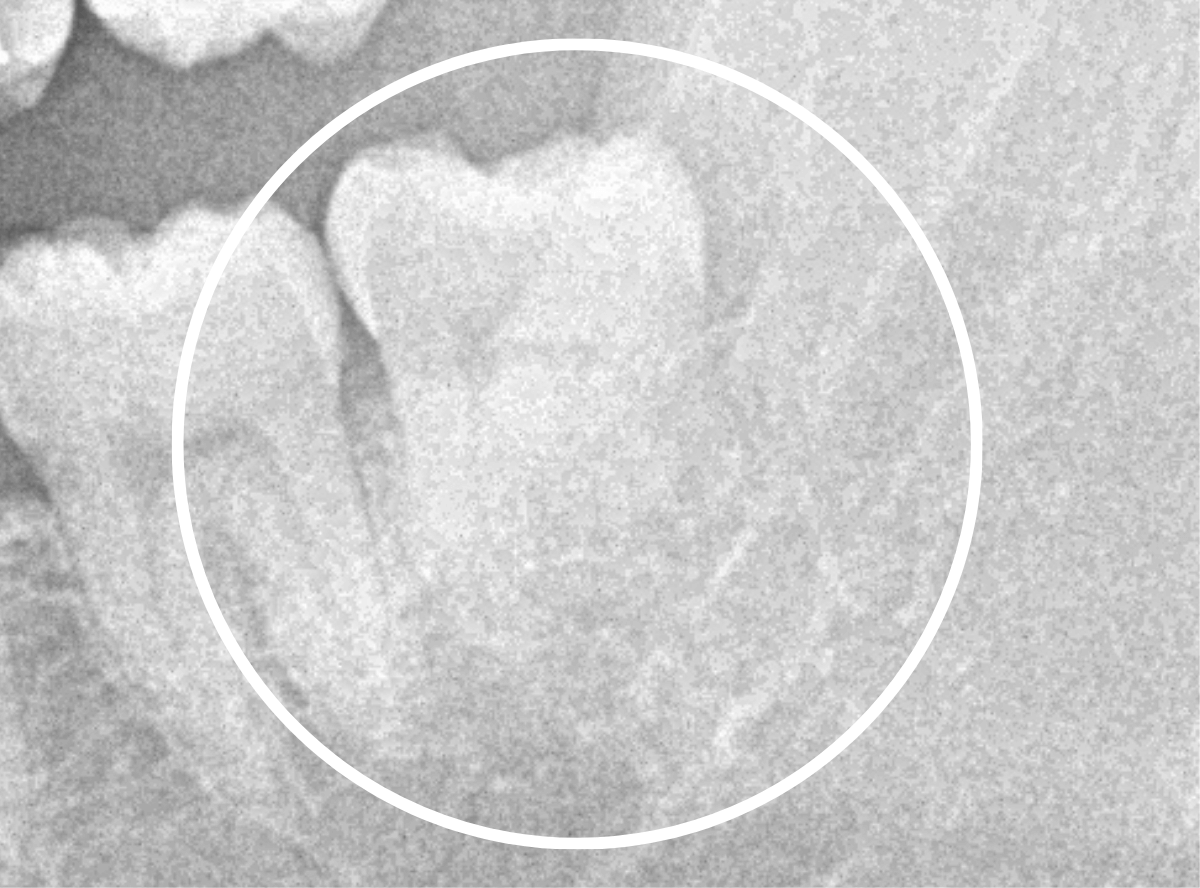

ここでは、比較的簡単なおやしらずの抜歯の例を中心にご紹介します。

このようなおやしらず、あなたはありませんか?